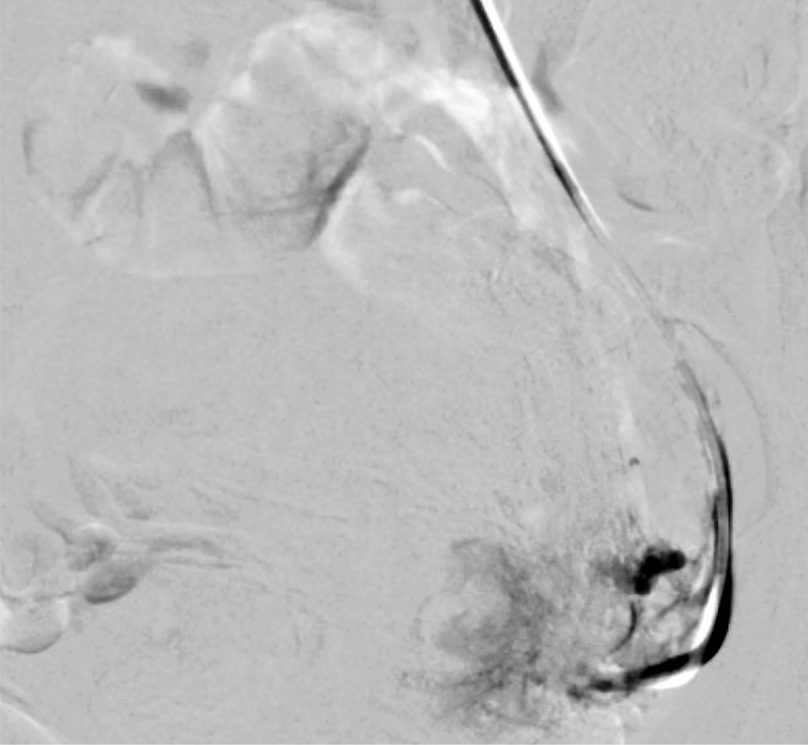

Выполнены пункция и катетеризация правой лучевой артерии в ретроградном направлении. Далее катетером выполнена селективная катетеризация правой и левой маточных артерий. Выявлена миома матки больших размеров с выраженным перифиброидным сплетением. При проведении ангиографии брюшной аорты и таза дополнительных источников кровоснабжения не выявлено. Катетер по проводнику проведен последовательно в горизонтальные сегменты левой и правой маточных артерий, питающих узлы (рис. 8, 9). Проведена эмболизация насыщенными гадотеридолом микросферами до стаза контраста в дистальных сегментах маточных артерий. Рентгеновский контроль эффективности эмболизации – рис. 10, 11. Катетер и интродьюсер удалены. Наложена давящая асептическая повязка.

Рис. 8. Клинический пример №2. Ангиограмма правой маточной артерии до ЭМА. / Fig. 8. Clinical case 2. Angiogram of the right uterine artery before UAE.

Рис. 9. Клинический пример №2. Ангиограмма левой маточной артерии до ЭМА. / Fig. 9. Clinical case 2. Angiogram of the left uterine artery before UAE.